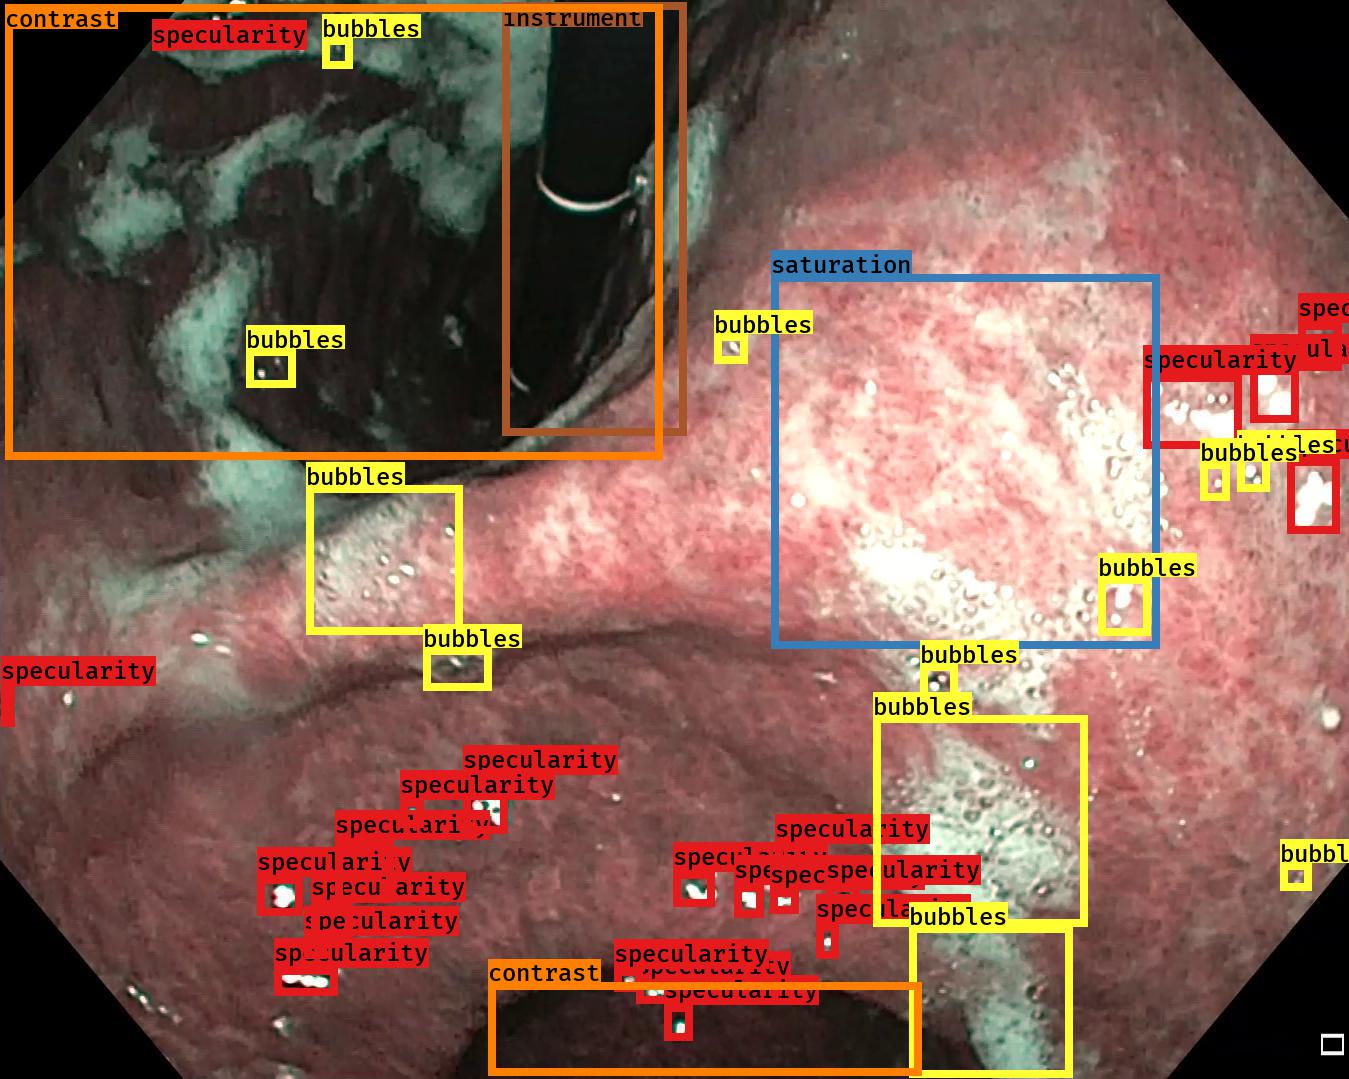

Examples for bounding box annotations for detection are shown in Fig. 2. It can be observed that while multiple boxes are annotated for several small specular areas; contrast, blur and instrument have relatively larger areas. Due to the overlap between two or more classes, the annotation by experts varied. This was minimized by following the detailed annotation protocol above. For semantic segmentation, a larger area mask was preferentially used to delineate locally very cluttered small specularity artifacts (see Fig. 3).

The minimal box sizes were used to describe the artifact region, e.g. if there are lots of specular reflections present in an image then instead of one large box we use multiple small boxes to capture the natural size of the artifact

For the same region, multiple boxes were annotated if the region belonged to more than 1 class